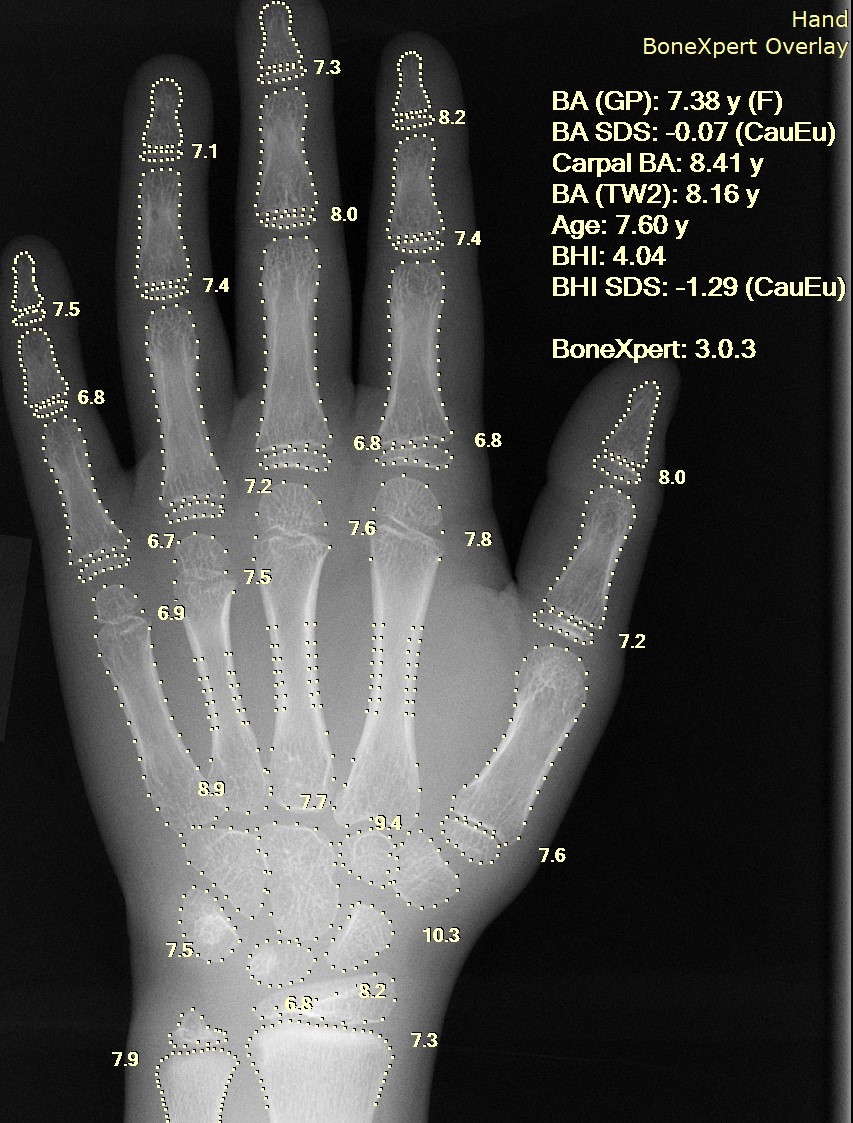

FFT 알고리즘, 이미지 처리, 음성 인식, 데이터 압축, 음성 합성은 데이터 처리의 주요 분야이다.[1] 정보는 이미지, 음향, 비디오 또는 기타 멀티미디어 형태를 취할 수 있으며, 정보의 비트는 신호를 통해 스트리밍될 수 있다.[1] 데이터 처리는 정보학의 중심 개념이며, 정보 처리 알고리즘을 연구한다.[1] 이 분야는 정보 이론, 통신, 정보 공학에서 중요한 역할을 하며, 의료 영상 컴퓨팅 및 음성 합성 등에 응용된다.[1]

의료 정보학 | ![]() |